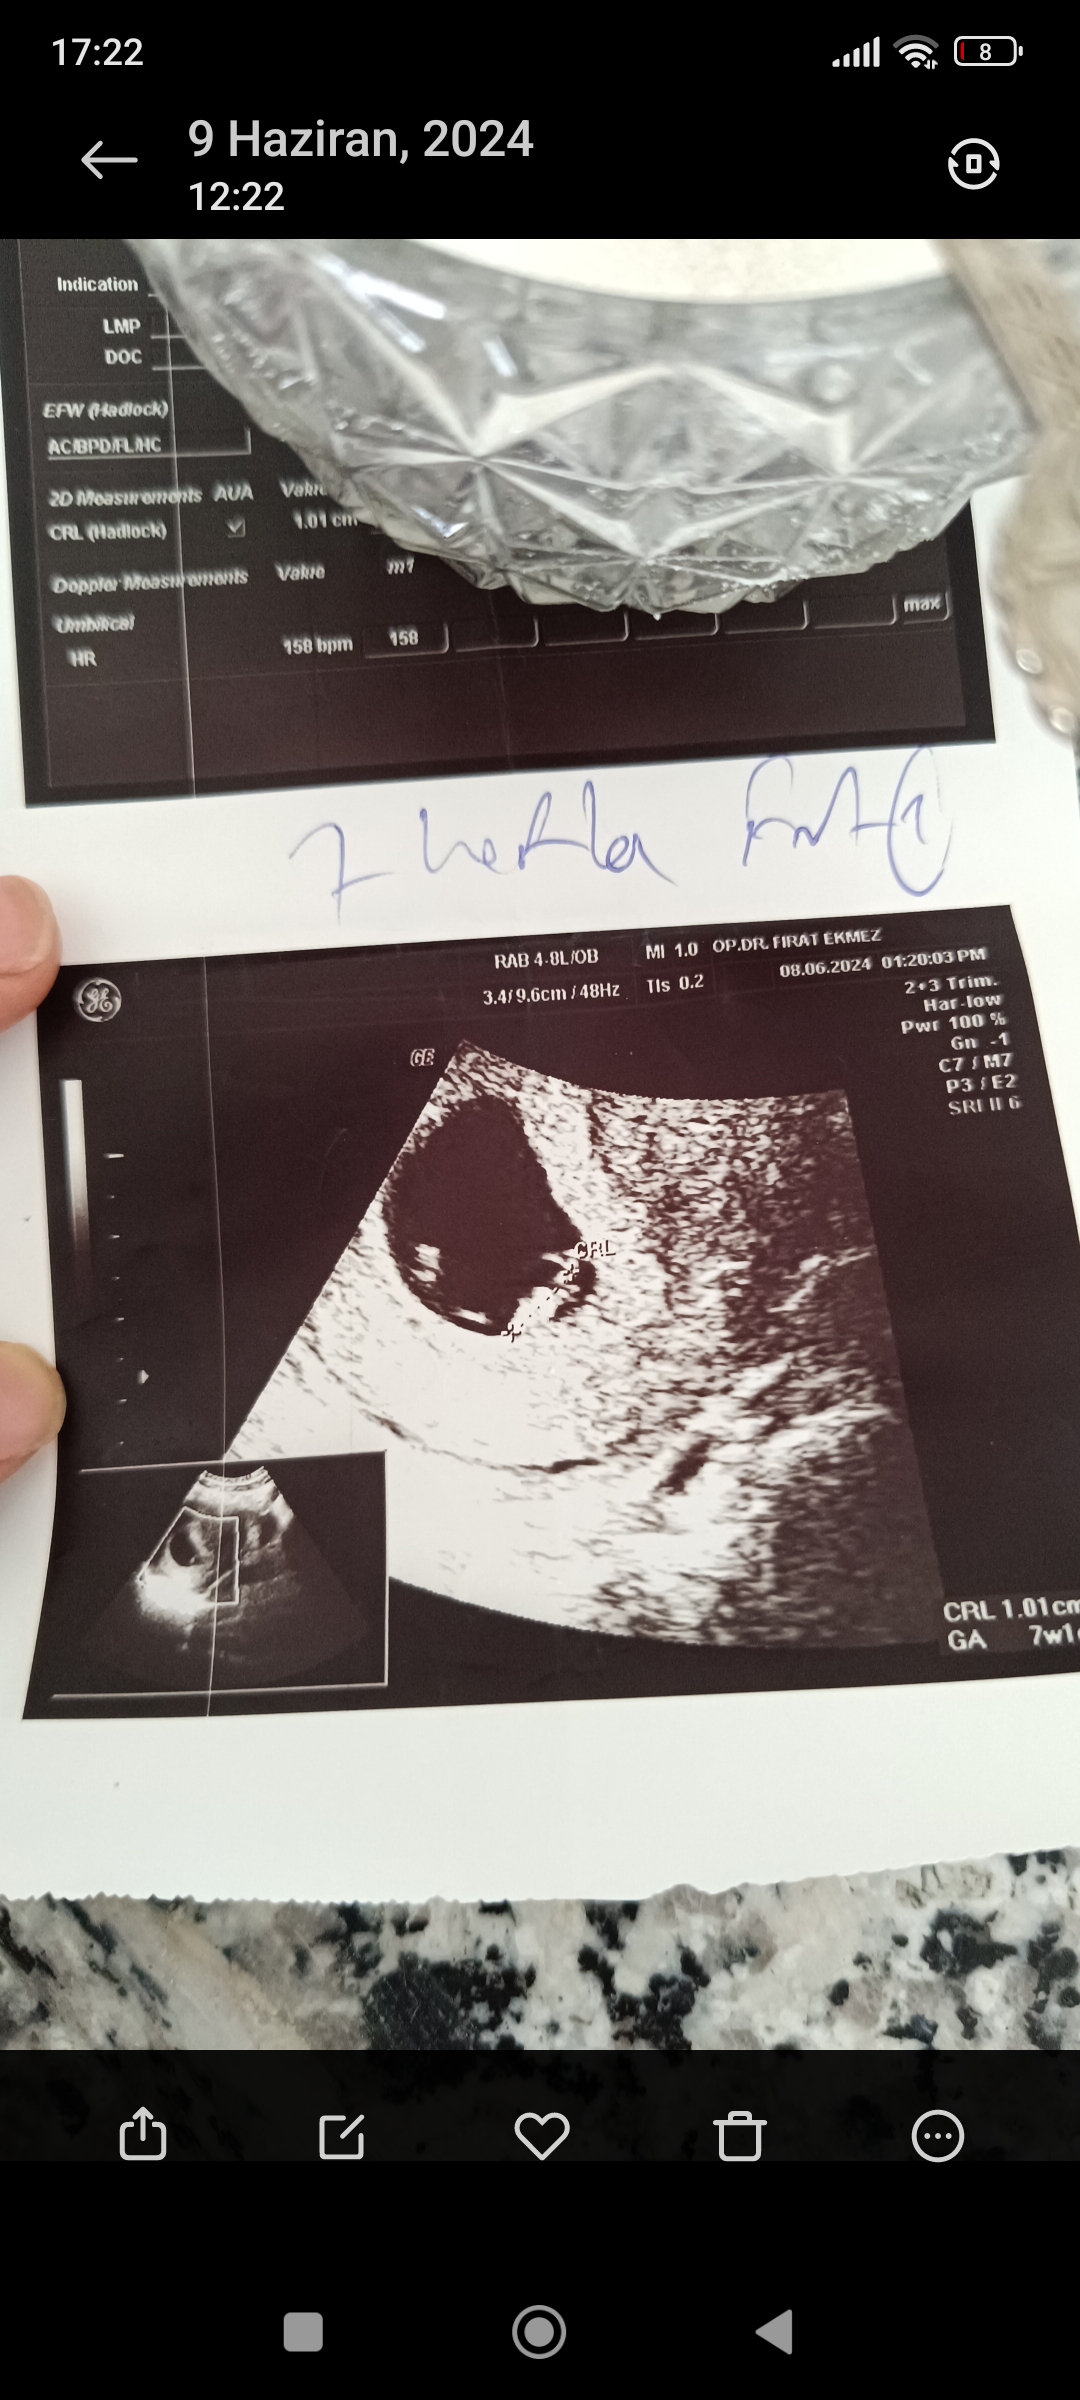

S sena deniz Kayıtlı Üye Katılım 9 Haziran 2024 Mesajlar 7 9 Haziran 2024 #1 Kızlar haftalık olduk cinsiyet tahmini yapabilir misiniz

AYŞENUR🦋 🔥 Kayra Ateş 🔥 💫 Ayra Nur 💫 Yönetici Mod Katılım 15 Ekim 2021 Mesajlar 33,844 Konum Kırklareli 11 Haziran 2024 #15 sena deniz' Alıntı: Sağol canım hemen yüklüyorum Mesajınız bir önceki mesaj ile otomatik birleştirildi 11 Haziran 2024 Ekli dosyayı görüntüle 5186 Mesajınız bir önceki mesaj ile otomatik birleştirildi 11 Haziran 2024 Buyrun tahminler bir kzizim var Allah'tan hep hayırlısını istiyorum merekta ediyor tabi insan c Genişletmek için tıkla ... Allahım miniick yarabbim . Rqbbim sağ Salim kucağına almayı nasip etsin inşallah canım kızın varmış birde oğluşun olur umarım sağlıklı bir şekilde Oyla 0 Downvote